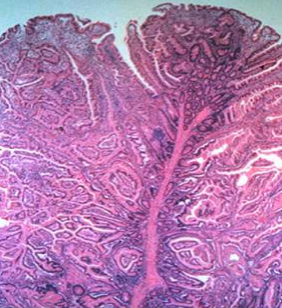

On gastrointestinal endoscopy, the PJP have no major distinguishing features, and may be sessile, pedunculated, or lobulated. The number of polyps ranges from 1 to more than 20 per segment of bowel, although some patients have solitary lesions. The size of the polyps ranges from 0.1 to more than 5 cm in diameter (picture 2). On histology, PJ P are hamartomas that characteristically contain a proliferation of smooth muscle extending into the lamina propria in an arborization-like fashion; the overlying epithelium is normal (picture 3). Epithelial misplacement involving all the layers of the bowel has been reported in  approximately 10 percent of small intestinal polyps in PJS. Epithelial misplacement, possibly due to mechanical forces, may extend into the serosa and be misdiagnosed as a well-differentiated adenocarcinoma.

Picture 3: Low power view of a duodenal PJP shows a tree-like proliferation of smooth muscle lined by normal small intestinal epithelium; the overlying epithelium is normal.